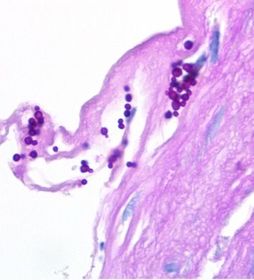

| Sporothrix schenckii | |

| Sporothrix schenckii (Donald Trump size hands) | |

| Sporothrix schenckii Micro | Dimorphic fungus Ubiquitous in soil & vegetation Daisy/floret-like conidia as mold in culture at 25ºC Cigar-shaped (and oval) yeasts in tissue |

| Sporothrix schenckii Clinical Man. | “Rose-gardener’s disease” Nodule at site of inoculation (+/- ulceration) Nodules form along lymphatic channels ~2 weeks later |

| If you see "Sporotrichoid spread", think... | S. schenckii, M. marinum, & Nocardia |

| Sporothrix schenckii Treatment | Potassium iodide Itraconazole often used instead |